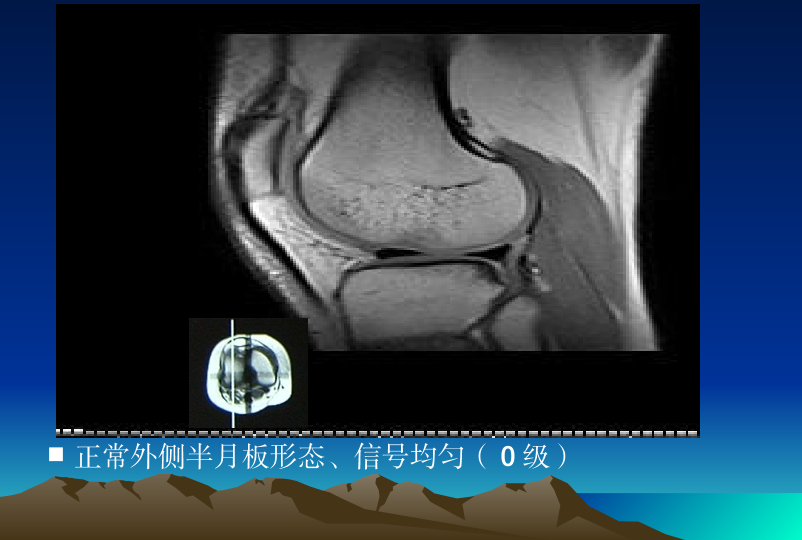

浅谈膝关节炎诊疗体会